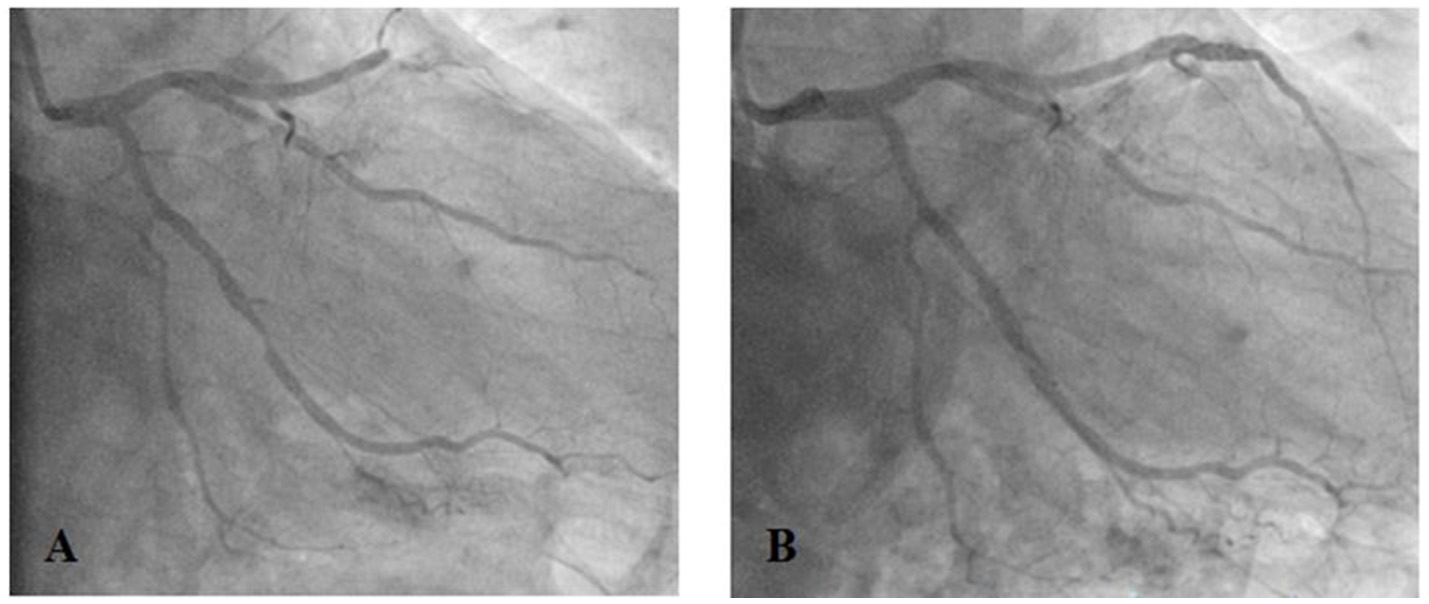

Due to the diagnosed non-ST-elevation MI coronary angiography was performed. The exam showed a proximal occlusion of the left anterior descending (LAD) artery and significant (80%) stenosis of the circumflex (CX) artery (Farooq et al., 2012), which were treated by implantation of two polymer-free drug eluting stents (DES) (Cre8 3 × 25 mm into the LAD, Cre8 3.6 × 16 mm into the CX) (Figure 1).

Figure 1

Proximal occlusion of the left anterior descending artery (LAD) and significant (80%) stenosis of the circumflex artery (CX) (A) treated by implantation of drug eluting stents (Cre8 3 × 25 mm into the LAD, Cre8 3.6 × 16 mm into the CX) (B).